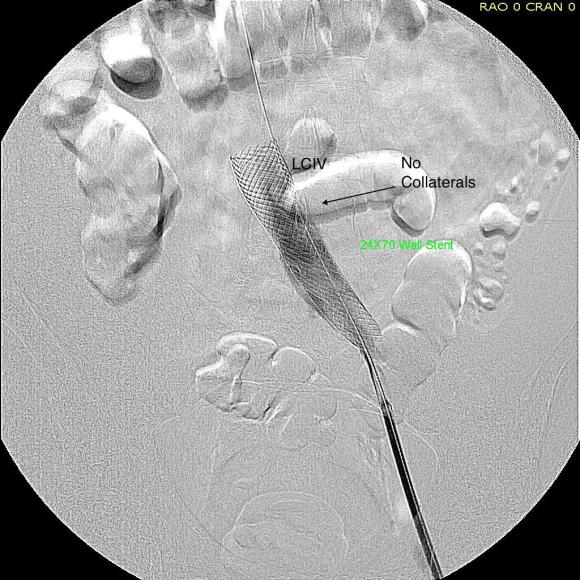

A 22mm Wall Stent was positioned across this and dilated with a 22mm balloon in the IVC and an 18mm balloon in the iliac vein. The resulting venogram showed resolution of the obstruction with collateral veins no longer visualized (below).

But again, IVUS demonstrated more directly the result (and illustrates the importance of having IVUS available for venous interventions).